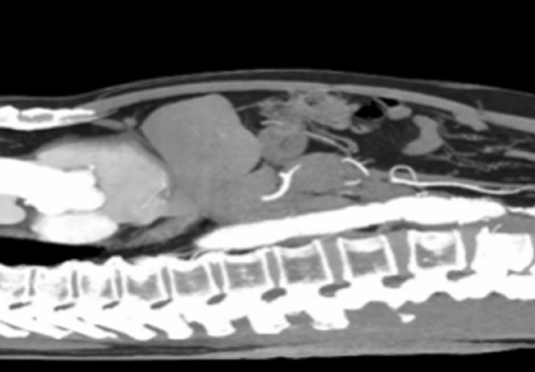

微创射频消融术

适用于微创射频热消融术治疗患者,引进权威医疗团体辅助引流。